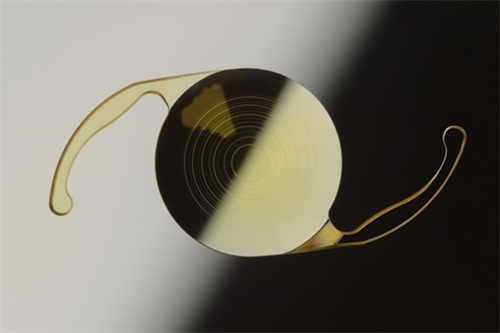

无衍射环设计:

传统多焦点晶体依赖衍射环分割光线,易产生光晕干扰;艾无极采用高阶渐进折射技术,光学区度数从周边向中央平滑递增,形成连续焦深,实现33厘米至无限远的平滑过渡。

光学建模突破:

通过***光线追踪模拟,优化晶体前表面曲率,实现焦深延长。